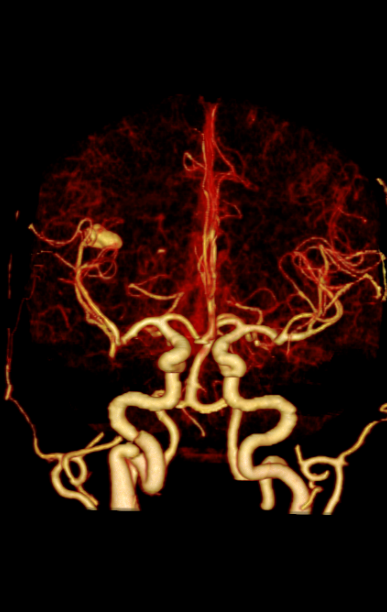

天河640可实现单圈扫描的全脑覆盖成像。采用宽体采集进行头部平扫、动态CTA及CTP成像,一次检查即可获得全脑平扫图像、动静脉造影图像和灌注图像。结合集成脑灌注分析、4D动静脉动态评估等高级后处理手段,不仅可应用于急诊缺血性脑卒中的影像评估,还可助力脑血管畸形、脑动脉瘤等其他脑血管病的结构和功能评估。

图片说明:颅脑血管成像及脑卒中灌注成像